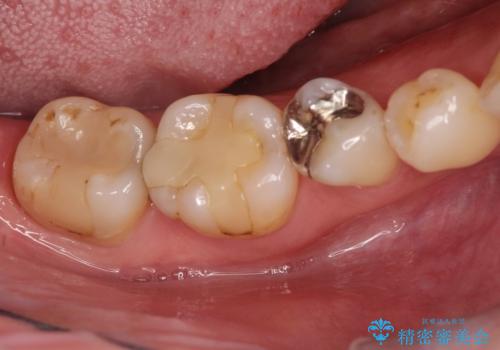

保険診療のCRインレーをセラミックインレーでやり直し

- 定期検診にて他院で治療された保険適用CRインレー部分(大臼歯2本)にむし歯を認めたため、セラミックインレーにて修復を行いました。

e-max プレスインレーにて修復治療を行っているため適合性及び審美性の高い治療を行うことができます